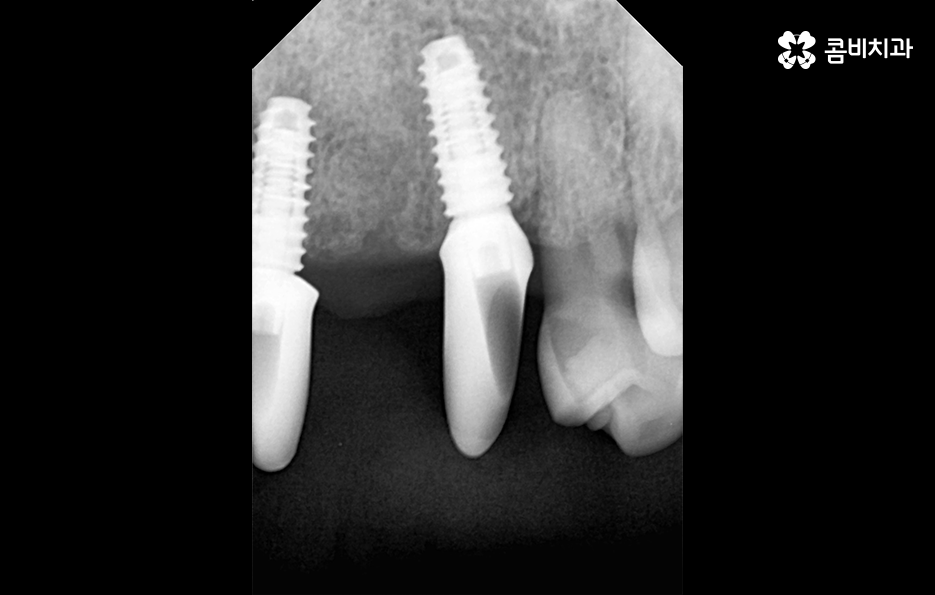

오늘 포스팅의 사례의 경우 앞니를 이미 잃은 상태였지만 주변 치아를 활용하여 브릿지로 연결해놓은 상태에서 기존의 치아가 버티지 못하여 앞니임플란트 하게 된 경우라고 볼 수 있는데요.

일반적으로 앞니임플란트의 경우 원데이임플란트라고 불리는 치아를 발치 후 즉시 임플란트를 식립하는 방법으로 치료하는 경우가 많은데 그 이유는 앞니의 특성상 심미적으로 중요하기 때문에 빠른 치료를 통해 임시치아를 부착하여 심미적 부담감을 줄일 수 있고 잇몸 라인을 살리는데 원데이 임플란트 방식이 유리한 부분도 있어요

잇몸 상태와 전신 건강이 양호한 경우에는 원데이임플란트를 통해 앞니임플란트 치료를 많이 진행하지만 오늘 케이스처럼 이미 치아를 발치한 후 시간이 지난 경우나 치주염으로 인해 잇몸 뼈가 녹고 염증이 심한 경우에는 빠른 치료보다는 잇몸을 충분히 회복하여 건강하고 안전한 결과에 더 초점을 두고 있는데요.